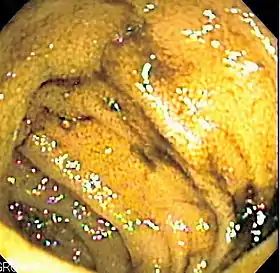

![]() Endoscopic image of normal small bowel. | |